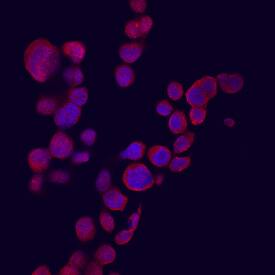

CXCL9/MIG antibody in THP-1 Human Cell Line by Immunocytochemistry (ICC).

CXCL9/MIG in THP‑1 Human Cell Line.

CXCL9/MIG was detected in immersion fixed THP-1 human acute monocytic leukemia cell line stimulated with IFN-gamma using Goat Anti-Human CXCL9/MIG Antigen Affinity-purified Polyclonal Antibody (Catalog # AF392) at 10 µg/mL for 3 hours at room temperature. Cells were stained using the Northern-Lights™ 557-conjugated Anti-Goat IgG Secondary Antibody (red; Catalog # NL001) and counter-stained with DAPI (blue). View our protocol for Fluorescent ICC Staining of Cells on Coverslips.